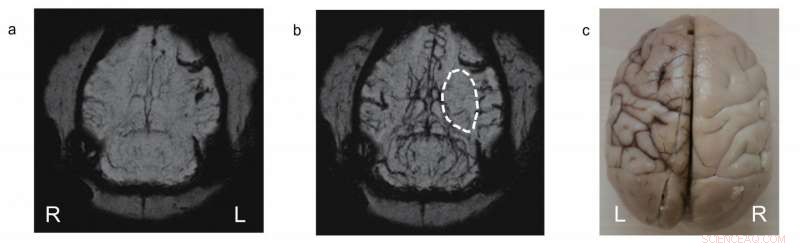

The PEG-IONCs contrast agent was used to dynamically follow an ischemia on the left side of a monkey's brain. After injecting PEG-IONCs (b) the details become clearer. Credit: IBS

Finally, after the successful use of PEG-IONCs in static MRA, the scientists conducted a more challenging dynamic imaging to see vascular flow patterns of cerebral ischemia (the cause of stroke) in dogs and monkeys. Cerebral ischemia is a disorder caused by insufficient blood flow to the brain and its early detection with MRI contrast agents is vital for survival of patients. In the experiment, images were taken at several time points, every 1.5 seconds after injection of the contrast agent to see the blood perfusion patterns in the brain. An occlusion in the middle cerebral artery was detected.